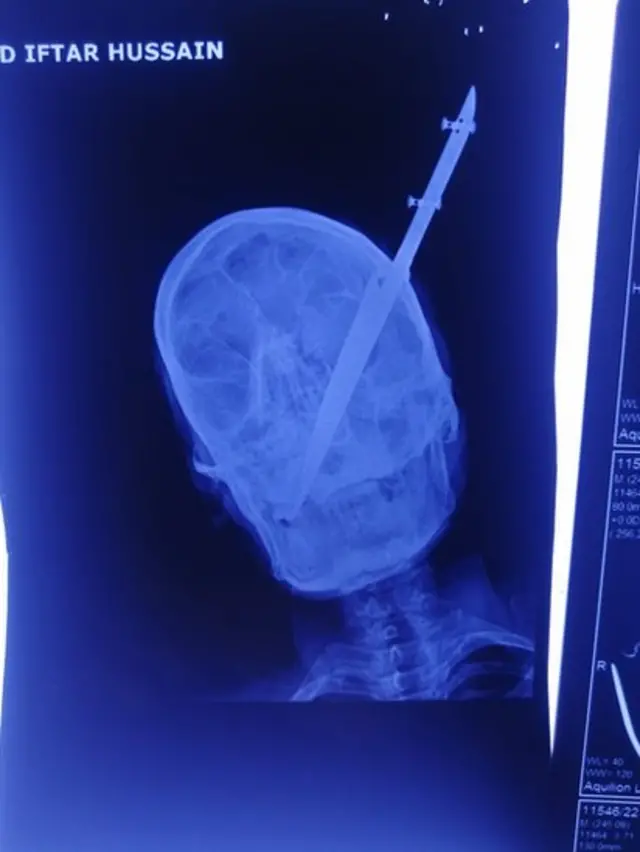

کراچی سے تعلق رکھنے والے افتار حسین شاہ کی آنکھ کے بالکل قریب چاقو جڑا ہوا تھا اور ایک کے بعد ایک ڈاکٹر ان کے علاج سے انکار کر رہا تھا۔

اس کا تیز دھاری حصہ جو کہ کم از کم پانچ انچ کا تھا، پورا کا پورا اندر چلا گیا تھا۔

کراچی کے جناح ہسپتال میں آنکھوں کے وارڈ میں داخل 32 سالہ افتار بتاتے ہیں کہ یہ چاقو انھیں ایک گھریلو جھگڑے کے دوران آنکھ کے قریب لگا تھا۔ اس واقعے کا مقدمہ کراچی کے اتحاد ٹاؤن تھانے میں درج کیا گیا ہے۔ افتار حسین شاہ کا الزام ہے کہ وہ گھر میں بیٹھے کسی معاملے پر بات چیت کر رہے تھے جب مبینہ طور پر ان کے بہنوئی نے انھیں قریب ہی پڑی چھری سے مارا۔ پولیس کا کہنا ہے کہ وہ ملزم کو گرفتار کرنے کی کوشش کر رہے ہیں۔

'ابتدائی طور پر جو ایکسرے کیا تھا اس میں کچھ سمجھ نہیں آ رہا تھا کہ چاقو کہاں تک گیا ہے اور اس نے کہاں تک کیا کیا نقصان پہنچایا ہے۔'

ان کا کہنا تھا کہ 'مریض کا سی ٹی سکین کروایا گیا تو اس میں پتا چلا کہ چاقو آنکھ کے قریب سے گزرتا ہوا ناک کے راستے، حرام مغز اور پھر گلے تک پہنچ چکا تھا۔ چاقو کسی ایک حصے تک محدود نہیں رہا تھا۔'

ڈاکٹر محبوب داد کہتے ہیں کہ 'اس میں حیران کن بات یہ تھی کہ چاقو نے کسی بھی حصے کو متاثر نہیں کیا تھا۔ اس کی آنکھ بھی محفوظ تھی۔ آنکھ سمیت ناک، حرام مغز، گلا اور اس حصوں میں موجود شریانیں محفوظ اور ٹھیک تھیں۔ یہ مریض کی انتہائی خوش قسمتی تھی۔'